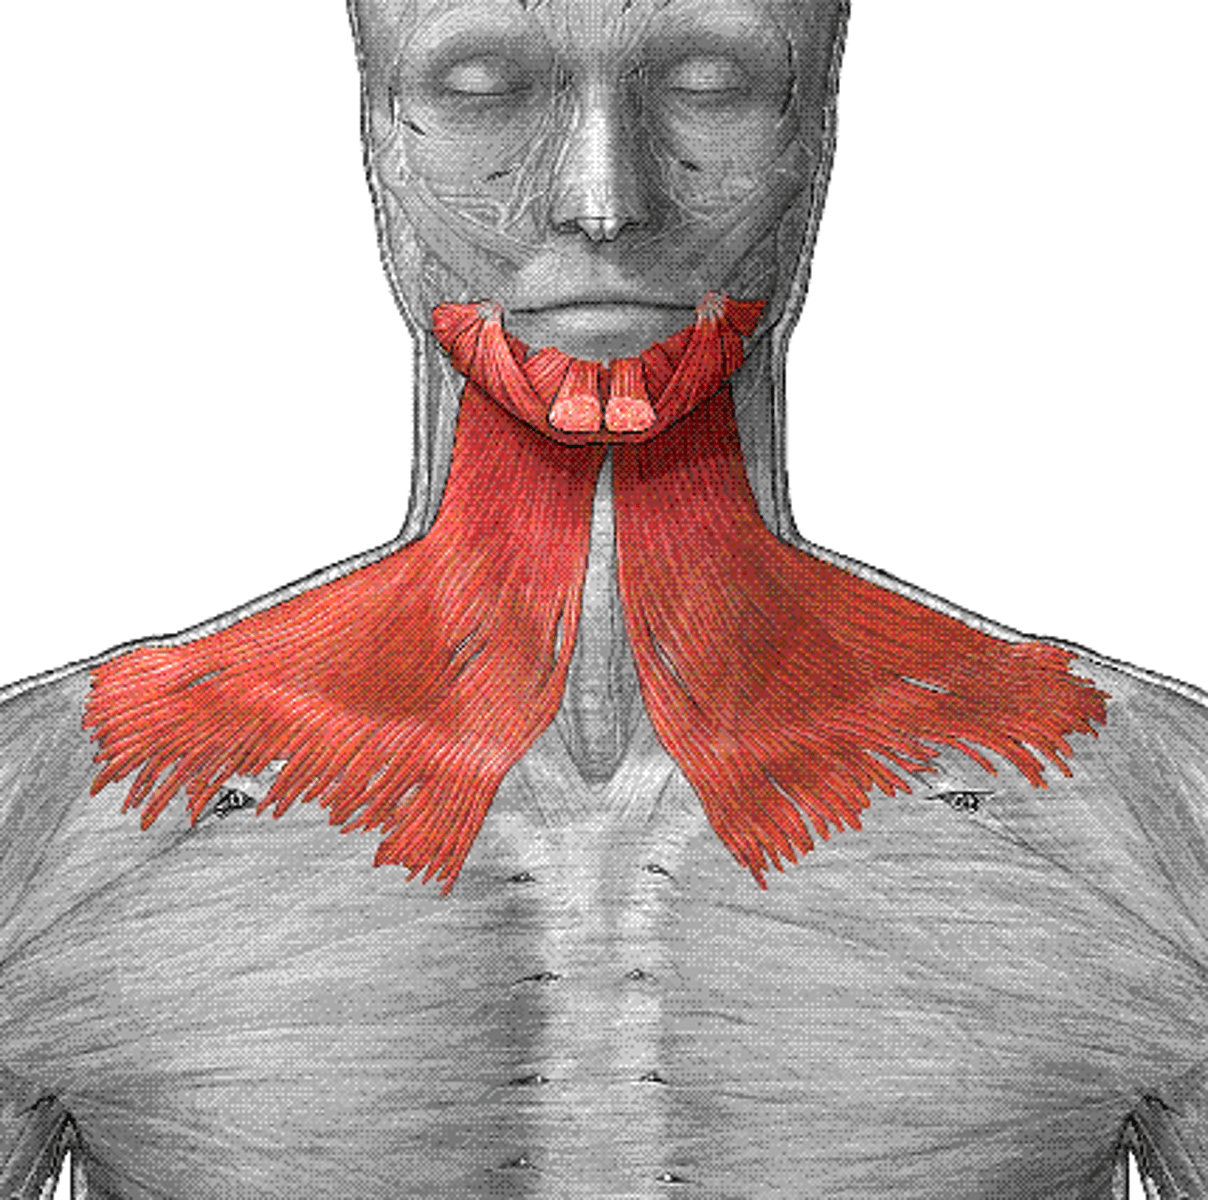

Platysma

A broad sheet of muscle fibers extending from the collarbone to the angle of the jaw